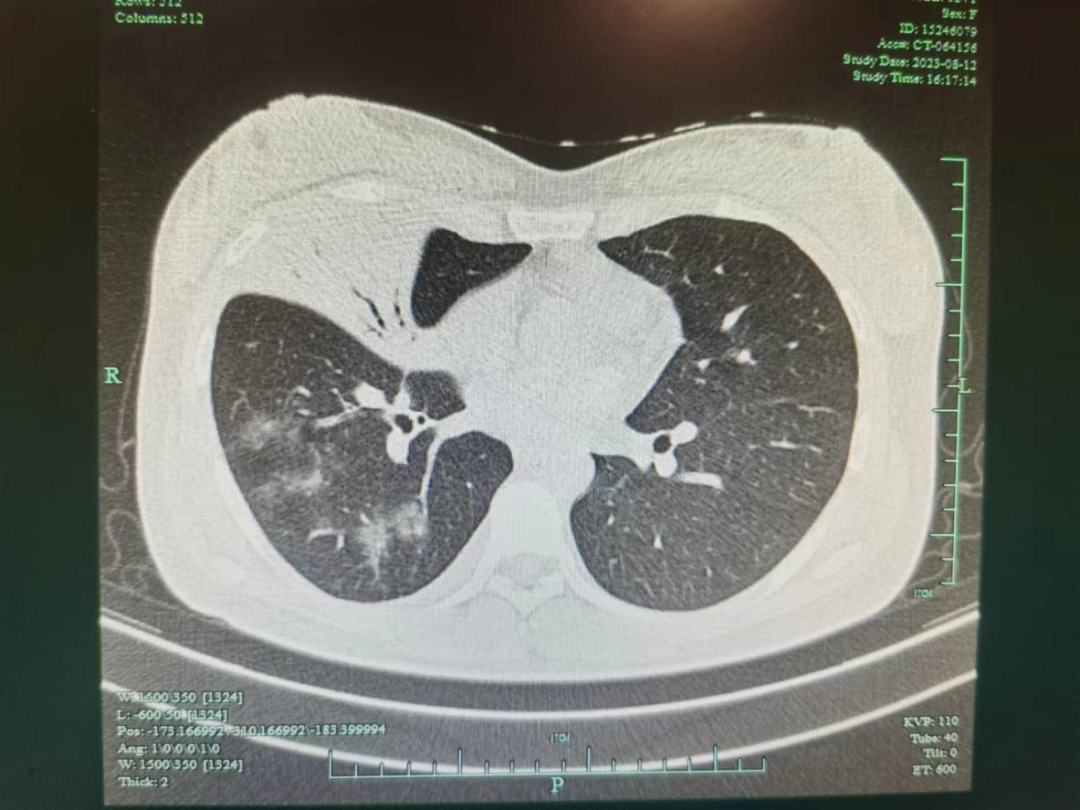

以为是小感冒,CT结果吓一跳

剧烈的咳嗽也让她辗转难眠,根本没办法休息好,虚弱的她开始忐忑不安,这样只会对宝宝不利。在家人的陪伴下,她赶紧来到临平区妇幼保健院内科就诊。

肺炎支原体感染会导致肺炎支原体肺炎,以间质性肺炎为主,有时会并发支气管炎。潜伏期大概是2-3周。